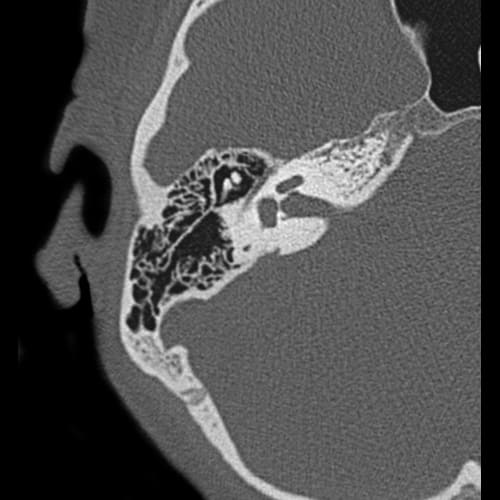

Coronal